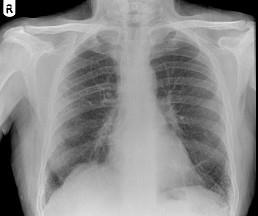

62岁,男,铸铁工,咳嗽、呼吸急促1个月,请结合胸片,选出最可能的诊断 ( )A.粟粒性肺结核B.肺结节病C.尘肺D.肺炎E.肺淤血

问题 62岁,男,铸铁工,咳嗽、呼吸急促1个月,请结合胸片,选出最可能的诊断 ( )

选项 A.粟粒性肺结核 B.肺结节病 C.尘肺 D.肺炎 E.肺淤血

答案 C